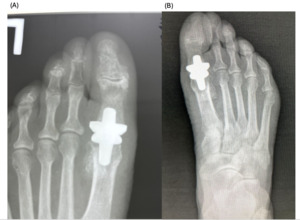

The patients had undergone radiographic evaluation of the MTP joint before the surgery, right after surgery, and 2 and 6 months after surgery (Figures 4-9). The radiographic imaging after the surgery confirmed the correct positioning and alignment. At the follow-up, the radiographic images were done to analyze the early healing process, to observe if there were any signs of implant loosening. 2 months after the surgery, no patient had periprosthetic radiolucencies, no stress-related changes. 6 months after surgery, no osteolysis, no migration of the implant.

._patient_a__immediate_postoperative_radiograph_(b).png)

._patient_a__6-month_follow-up_radiograph_(b).png)